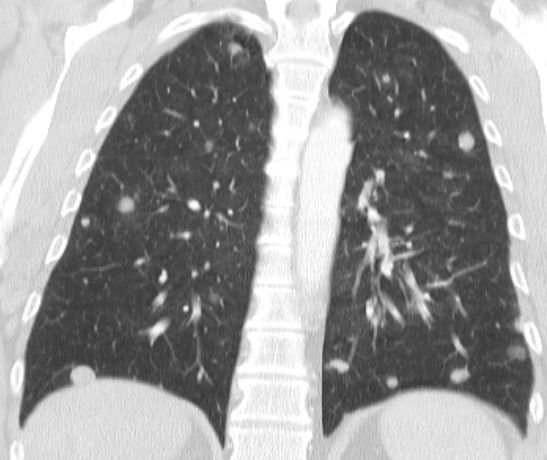

| Lunge | 75jährige Frau mit Magenantrumkarzinom. Miliare

pulmonale Aussaat.![]() |